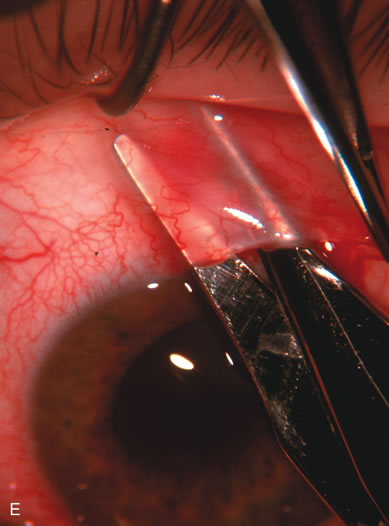

The inflammation associated with lens extraction at any site usually causes complete failure of a marginal functioning bleb. In addition, pressure reduction by medical means is usually minimal in these recalcitrant cases, and combined surgery is indicated. In the past, these cases were approached with large-incision ECCE, clear corneal cataract incision, and bleb revision. Drawbacks included those mentioned earlier for large incision clear corneal cataract extraction, and bleb revision is often associated with conjunctival buttonholes, wound leaks, subconjunctival hematoma, destruction of friable sclera, and associated hypotony. With the advent of modern-day cataract surgery, a phacotrabeculectomy is often possible adjacent to the failed filter (Fig. 7). The ability to combine cataract extraction with implant and filtration surgery all through the same small incision has greatly improved outcomes for patients with marginal preoperative filters. There are several other viable options in this case. If the surgeon elects to remove the cataract through a temporal clear corneal incision, the bleb may be revised or a new adjacent filter fashioned. As mentioned earlier, revising a failed filter is technically challenging. If the surgeon believes it is not feasible to revise the filter or fashion a new one, a glaucoma drainage implant is a reasonable option combined with temporal lens extraction.172

Fig. 7. Phacotrabeculectomy adjacent to a failed filter in cataractous eye. The ability to combine small-incision cataract extraction with trabeculectomy all through the same incision adjacent to the failed filter allows the surgeon to work in a familiar superior area. Avoiding incisions into the existing bleb decreases conjunctival buttonholes, hypotony, operating room time, and subconjunctival bleeding. A. Appearance of failed bleb with exposure of superior temporal quadrant gained with a corneal traction suture. B. Prepare a limbus-based conjunctival flap and a scleral flap. C. This bleb is at high risk to fail again justifying the need for MMC, 0.2 mg/cc applied on a pledget for 4 minutes. D. Insert the keratome and perform phacotrabeculectomy in the usual fashion.